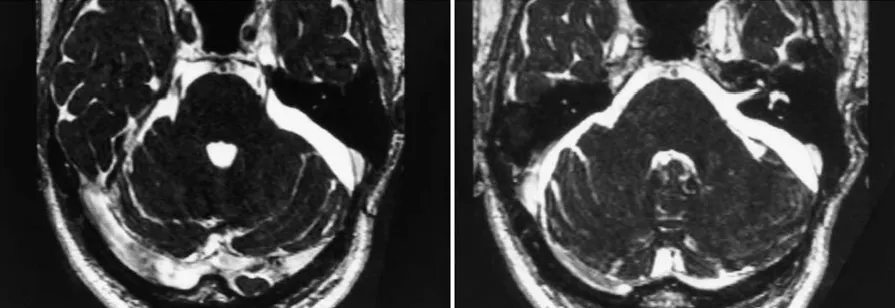

这是一个位于左侧桥小脑角(CPA)区和Meckel腔的表皮样囊肿。

轴位T1加权图像显示稍高信号病灶伴占位效应;箭头指示Meckel腔内的肿瘤。

轴位CISS图像显示稍低信号病灶延伸至Meckel腔。

轴位CISS图像显示内听道前方和Meckel腔内的稍低信号病灶(箭头指示)。